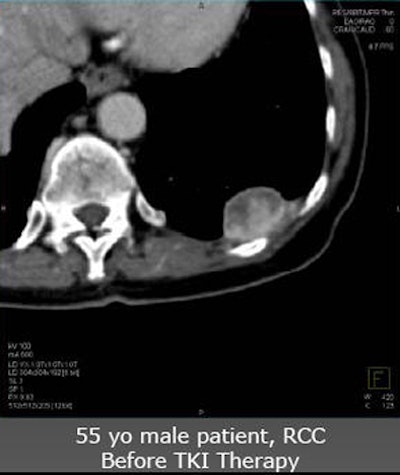

| Future studies will focus on clinical experience with angiogenic agents. In a patient with renal cell carcinoma with pleural metastasis (above), decreases in tumor perfusion are readily seen after three weeks of sorafenib antiangiogenic therapy (below). |

![]() |